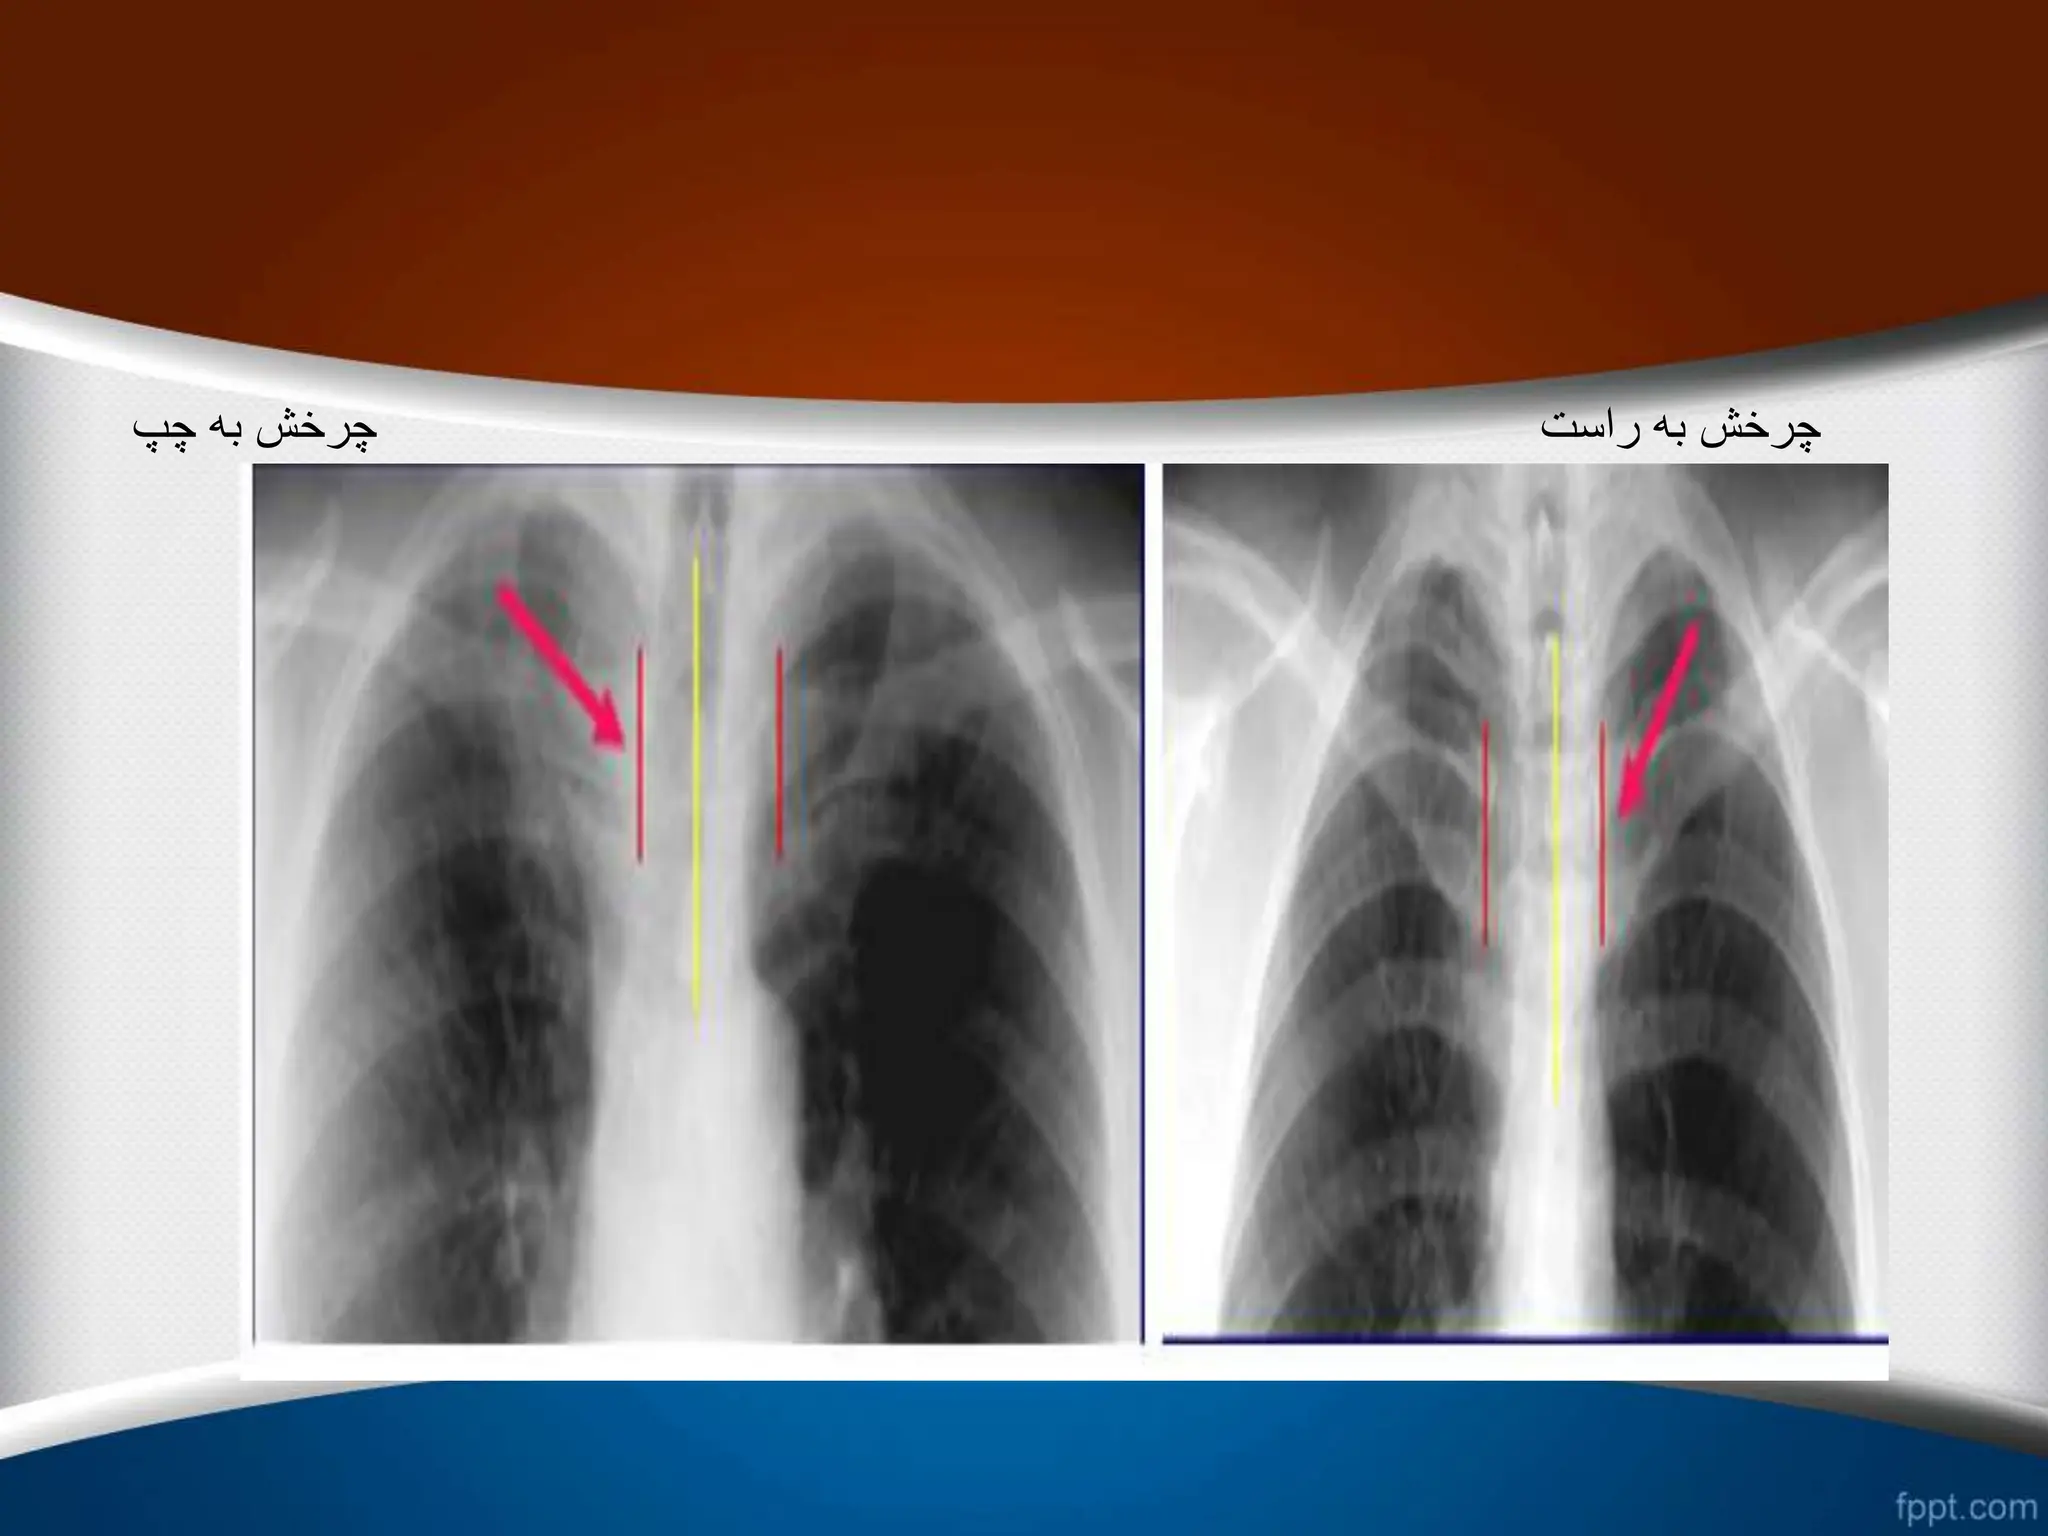

‫چرخش‬ –Rotation

•

‫حاشیه‬ ‫و‬ ‫کند‬ ‫پیدا‬ ‫تغییر‬ ‫قلب‬ ‫کلی‬ ‫شکل‬

‫نامنظم‬ ‫را‬ ‫قلب‬ ‫های‬

‫کند‬

.

(Abnormal configuration)

‫دهد‬ ‫قرار‬ ‫تأثیر‬ ‫تحت‬ ‫را‬ ‫ریه‬ ‫عروقی‬ ‫طرح‬

‫طرح‬ ‫که‬ ‫طور‬ ‫به‬

‫نزدیک‬ ‫اشعه‬ ‫به‬ ‫که‬ ‫سمتی‬ ‫در‬ ‫عروقی‬

‫در‬ ‫و‬ ‫کمتر‬ ‫است‬ ‫تر‬

‫شود‬ ‫دیده‬ ‫بیشتر‬ ‫است‬ ‫دورتر‬ ‫اشعه‬ ‫از‬ ‫که‬ ‫سمتی‬

‫چپ‬ ‫به‬ ‫چرخش‬

.1

‫بزرگتر‬ ‫قلب‬

.2

‫خونتر‬ ‫کم‬ ‫چپ‬ ‫ریه‬ ‫فیلد‬

‫راست‬ ‫به‬ ‫چرخش‬

‫کوچکتر‬ ‫قلب‬

‫خونتر‬ ‫کم‬ ‫راست‬ ‫ریه‬ ‫فیلد‬

‫چپ‬ ‫به‬ ‫چرخش‬ ‫راست‬ ‫به‬ ‫چرخش‬